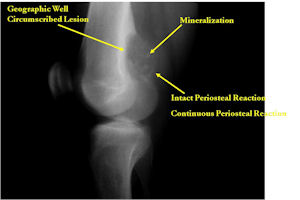

- Geographic, circumscribed lesion usually around 5cm in size.

- There may be expansion of bone, cortical thinning and cortical breakthrough. A soft tissue mass may accompany this lesion but the soft tissue component is usually contained by the periosteum.

- The periosteum remains intact around the soft tissue component. Might need a CT scan to detect the subtle calcification (Egg Shell Rim of Calcification) associated with an intact periosteal reaction

- The lesion may be entirely radiolucent but usually shows some degree of mineralization. Mineralization may appear stippled like cartilage but do not see chondroid pathologically. Mineralization is sometimes better detected on a CT scan rather than an x-ray.

- Usually less surrounding sclerosis than an osteoid osteoma.